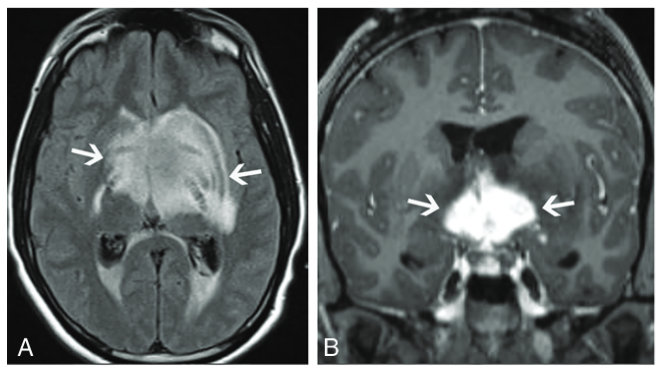

脳:辺縁系脳炎

画像所見

典型的な画像所見は内側側頭葉のT2高信号と腫脹である.時に,造影効果を伴う.FDG-PETでは代謝亢進を認めうる.

他の辺縁系の部位にもこれらの所見が生じることがある(視床下部や乳頭体に明瞭な病変を認め,他の辺縁系は保たれることがある).海馬や扁桃体などの典型的な部分が障害されていない場合でも考慮する必要がある.

時に辺縁系脳炎は占拠性病変に似た画像を呈し,low grade~high gradeグリオーマやリンパ腫と誤認されうる.